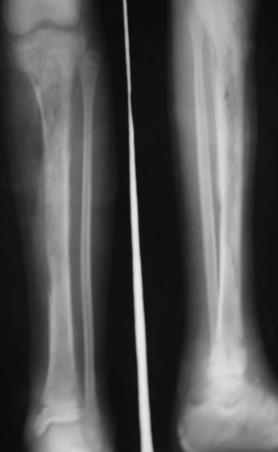

在上 1/3 折,由于儒腰肌、臀中肌、臀小肌和外旋肌的牵拉,使近折端向前、外及外旋方向移位;远折端则由于内收肌的牵拉而向内、后方向移位;由于股四头、阔筋膜张肌及内收 的共同 用而向近端移位。

中 1/3 骨折后,由于内收肌群的牵拉,使骨折向外成角

下 1/3 骨折后,远折端由于排肠肌的牵拉以及肢体的重力作用而向后方移位,又由于股前、外、内 牵拉的合 ,使近折端向前移位,断端重叠,形成短缩畸形

非手术治疗 3岁以下儿 采用垂直悬吊皮肤牵引在牵引过程中,要定时测量肢体长度和进行床旁X线检查,了解牵 力是否足够。若牵引力过大,导致过度牵引,骨折端出现裂隙,将会发生骨折延迟愈合或不愈合。;成人和3岁以上 的股骨干骨折近年来多采用手术内固定治疗 对于存在于术 忌证的,可行持续 10 卧床期间,需肌肉收缩训练,预防肉萎缩、关节粘连和深静脉血栓形成。床旁X线平片证实骨折愈合后,下地活动

手术治疗 成人股骨干骨折于术多采用钢板、带锁髓内钉固定。儿童股骨干骨折多采用弹性钉内固定;严重的开放性骨折可用外固定架治疗